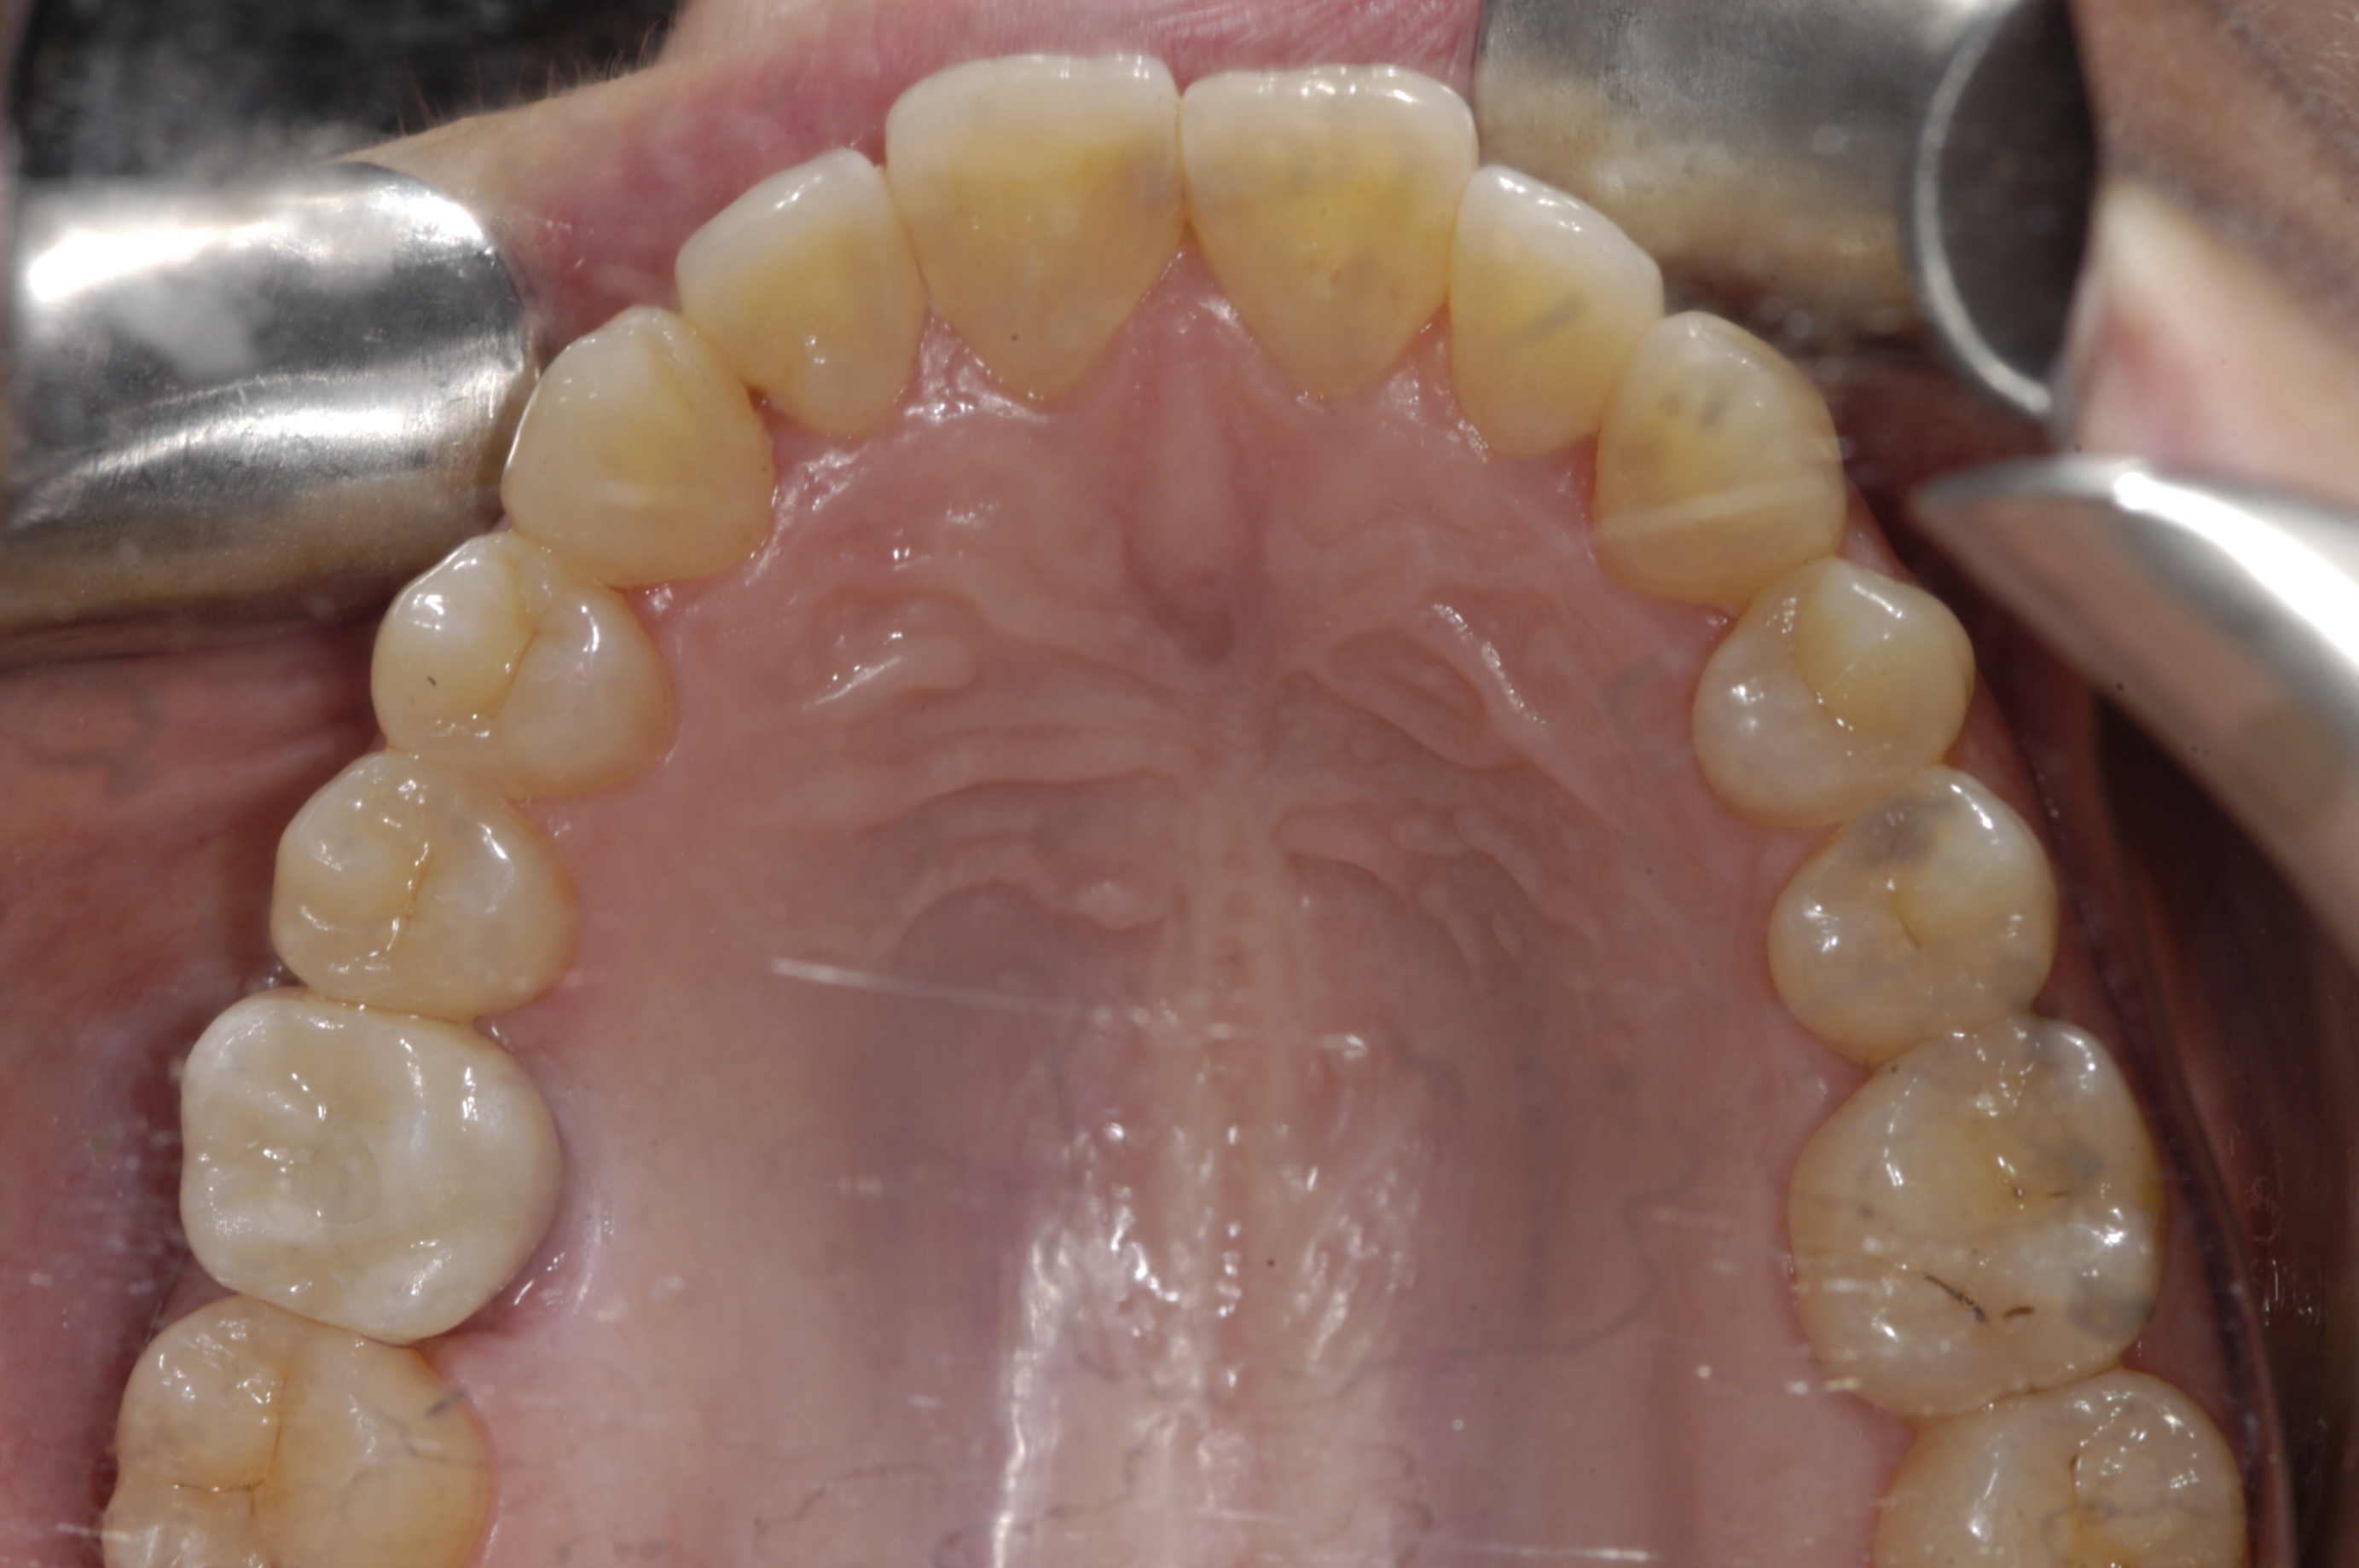

Finally, the amount of attached gingiva is evaluated. There is disagreement regarding the need for attached gingiva around implants,16,17 but the generally accepted minimum is 2 mm.18,19 A zone of 3 mm is recommended by this protocol for esthetics. A simple method of evaluation is to place a periodontal probe against the cementoenamel junctions of the adjacent teeth. At the midpoint between the adjacent teeth, the buccal aspect of the implant should exit 2 mm lingual to the probe. Therefore, if attached gingiva extends 1 mm facial to the probe, there should be adequate keratinized tissue. If the minimum requirements of bone volume and attached gingiva are not met, ridge augmentation and/or soft-tissue grafting are needed prior to implant placement. If the minimum requirements are met, digital impressions of both arches are obtained before dismissing the patient.

The first step is to design the desired restoration. If designed with CAD/CAM design software (Figure 1), the restoration will need to be saved in a file type that is compatible with the implant-planning software being used. If using an analog wax-up, the waxed up model will have to be scanned with either a laboratory scanner or a chairside CAD/CAM scanner and saved in a compatible file type.